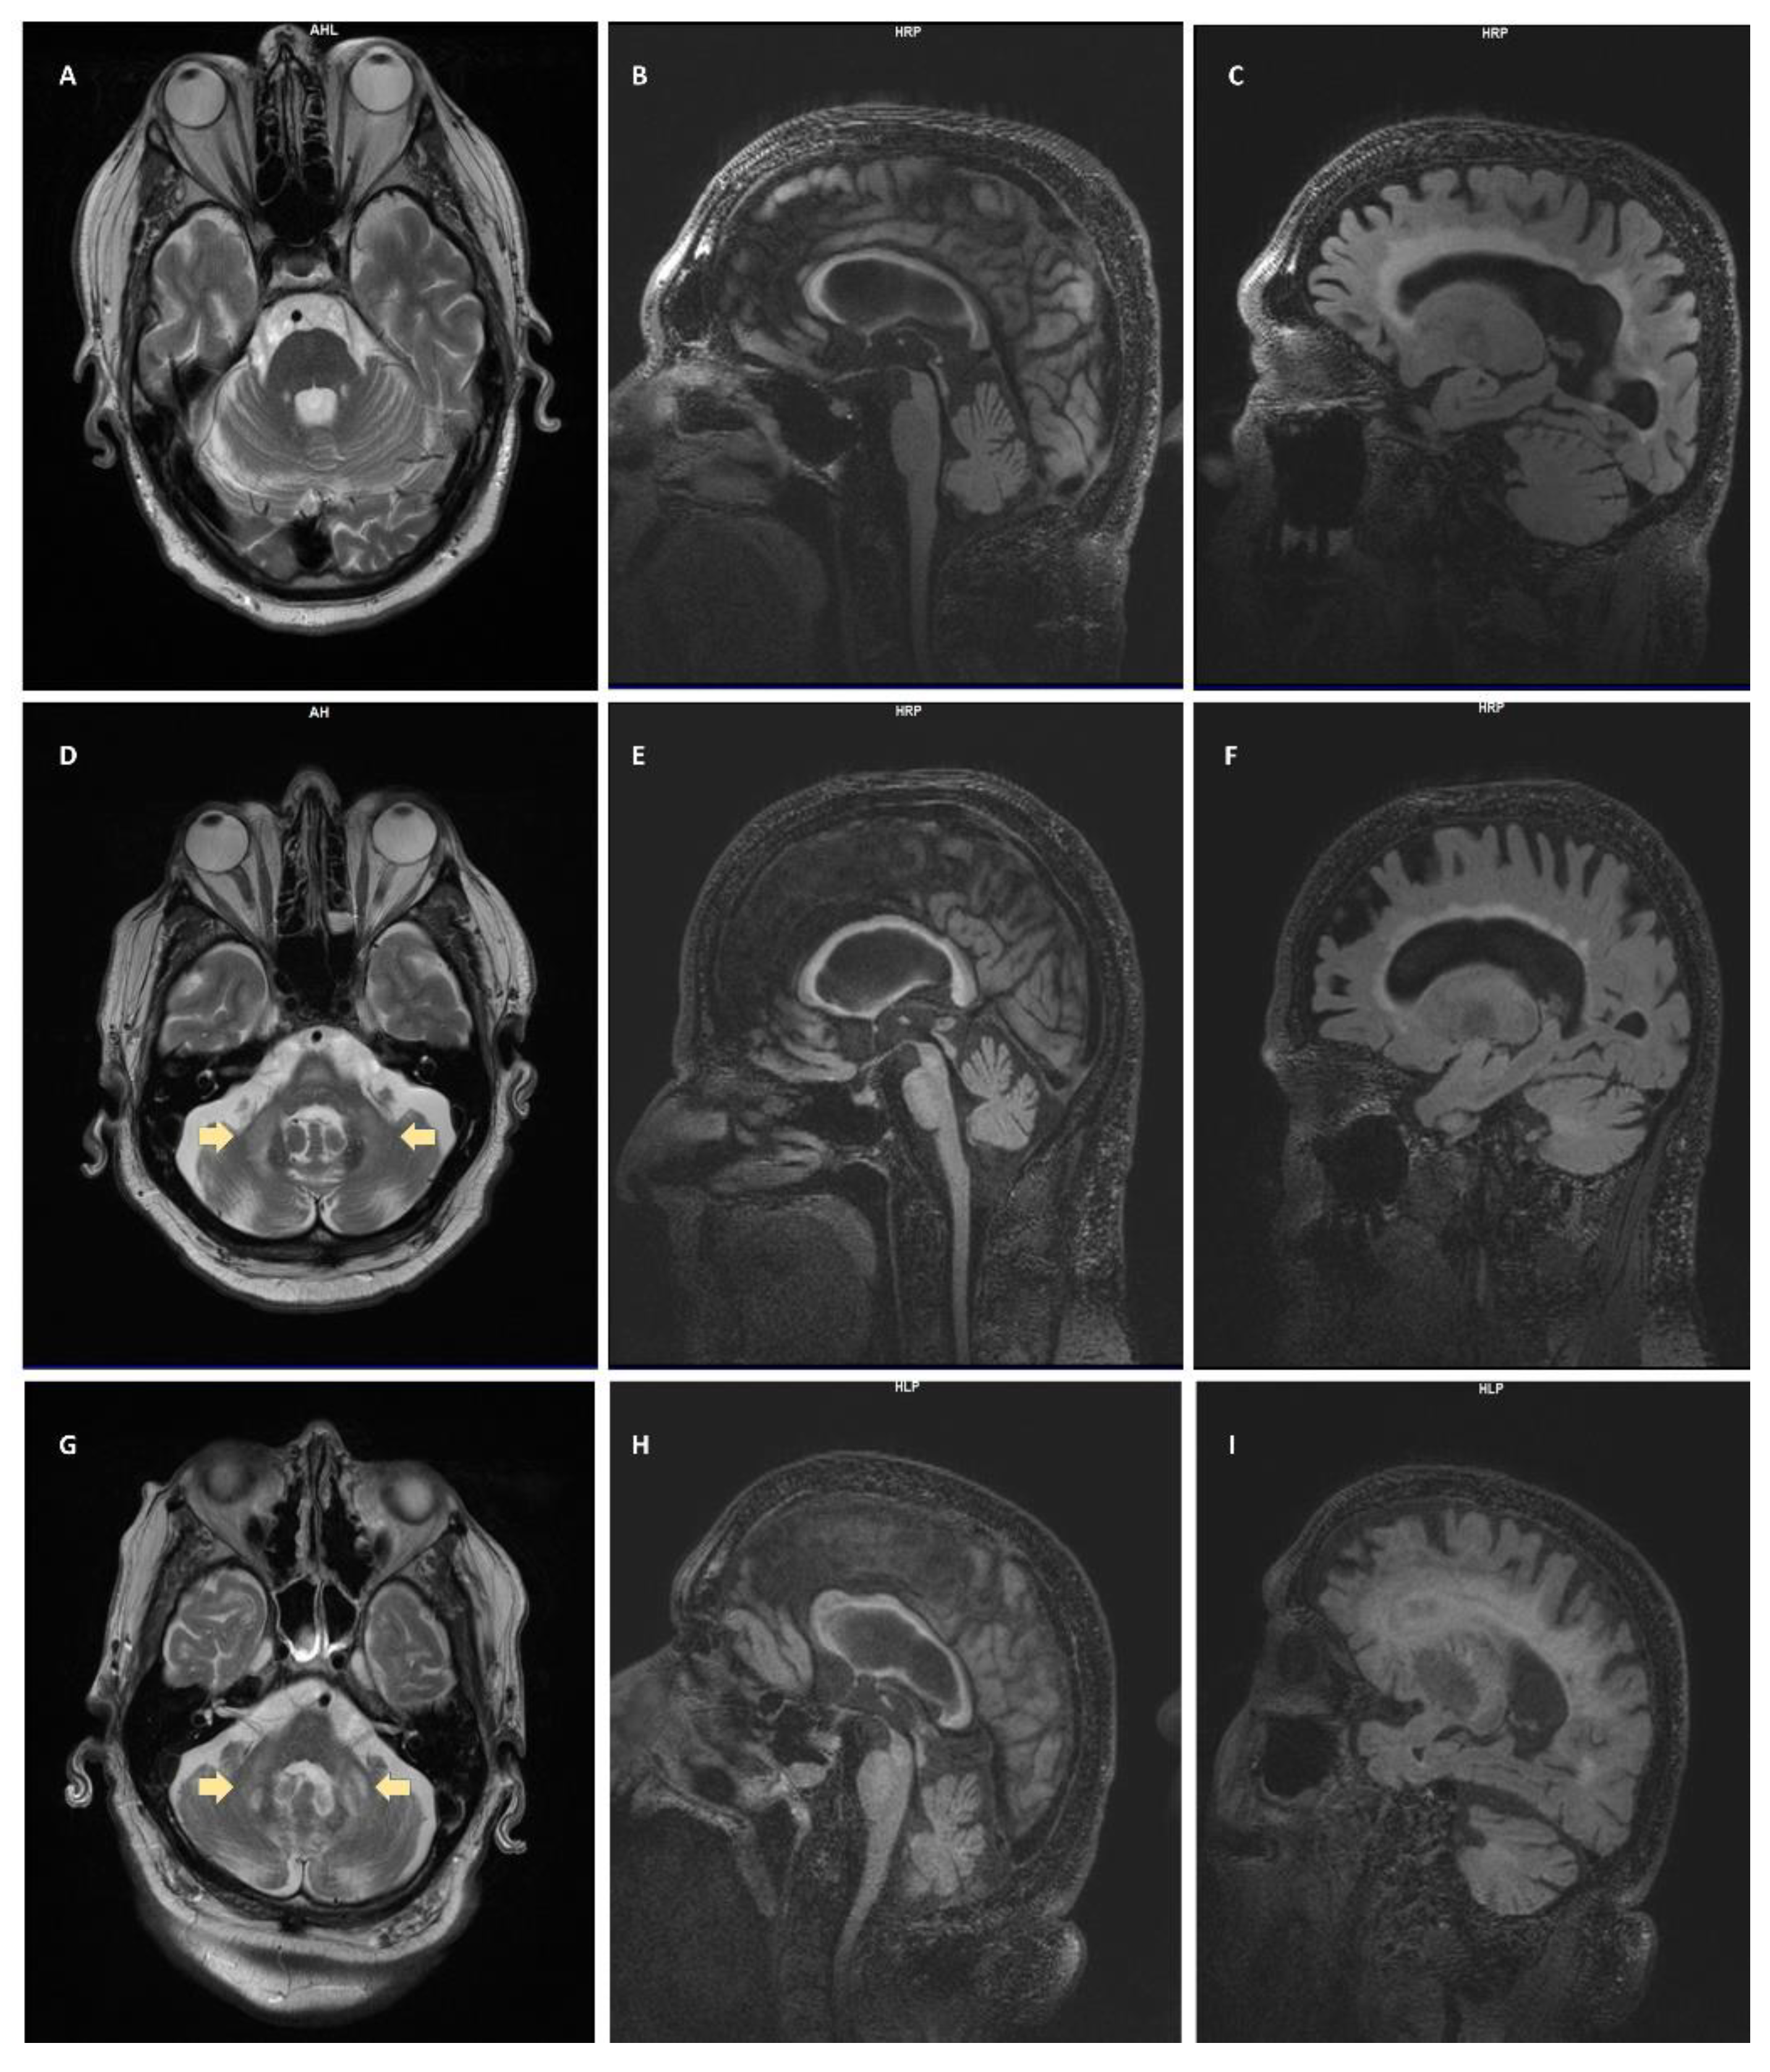

4.3. Neuroradiologic Findings

| Case | CGG Repeat Size | Age of Onset | Presenting Neurologic Symptom | Additional Medical Conditions | Labs | MRI Findings | Current FXTAS Stage |

|---|---|---|---|---|---|---|---|

| 1 | 126 | 57 | Gait problems | Skeletal hyperostosis, sleep apnea, erectile dysfunction, minor depression | CBC: normal CMP: normal Homocysteine: 9.2 TSH: normal HbA1C: 5.9% | Ventriculomegaly, WMD, splenium sign, mild–moderate cerebral atrophy | III |

| 2 | 94 | 63 | Gait and balance problems | GERD, hypertension, type 2 DM, hearing loss, swallowing problems | CBC: normal CMP: normal Homocysteine: 14.3 (high) TSH: normal HbA1C: 6.2% | MCP sign, WMD, splenium and genu sign, thinning of corpus callosum ventriculomegaly, prominent perivascular spaces | V |

| 3 | 91 | 62 | Ataxia | CAD, hypertension, hypercholesterolemia, anxiety, irritability, moderate dementia | CBC: normal CMP: normal Homocysteine: 10.7 TSH: normal HbA1C: 6.3% | WMD, splenium sign, cortical atrophy, MCP sign | V |